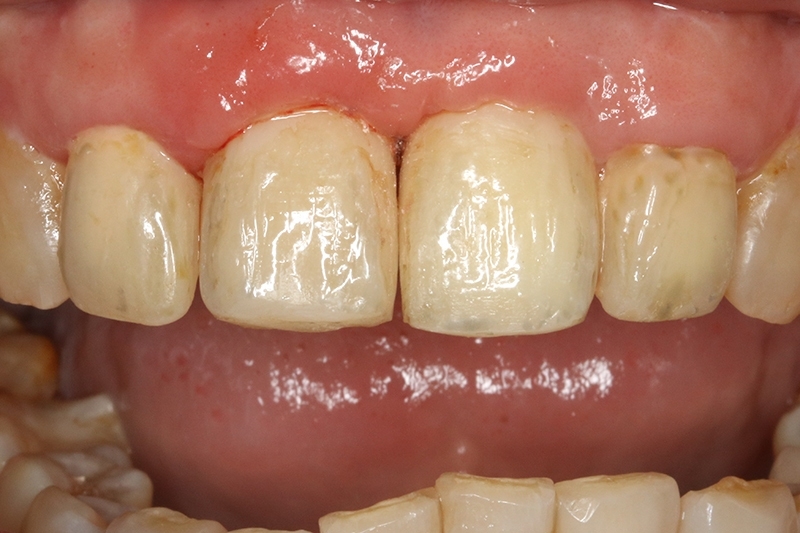

經過牙周治療後,控制發炎,可見牙齦的狀況變得更健康了!

接續牙周治療完成後的療程,上排門牙植牙的問題處理,長期不斷的發炎化膿流血,除了造成周圍組織發炎與牙齦腫脹,同時造成齒槽骨被細菌破壞與吸收,根本解決的方式是建議移除感染與位置不佳的植體,先進行植牙移除手術+齒槽骨保存術,先使用膠原蛋白促進軟組織癒合,加快癒合的速度。